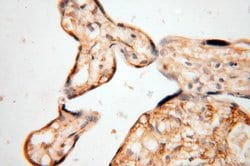

SYK Rabbit anti-Human, Mouse, Rat, Polyclonal, Proteintech

This gene encodes a member of the family of non-receptor type Tyr protein kinases. This protein is widely expressed in hematopoietic cells and is involved in coupling activated immunoreceptors to downstream signaling events that mediate diverse cellular responses, including proliferation, differentiation, and phagocytosis. It is thought to be a modulator of epithelial cell growth and a potential tumor suppressor in human breast carcinomas. Alternatively spliced transcript variants encoding different isoforms have been found for this gene.Specifications

| Immunohistochemistry (Paraffin) | |